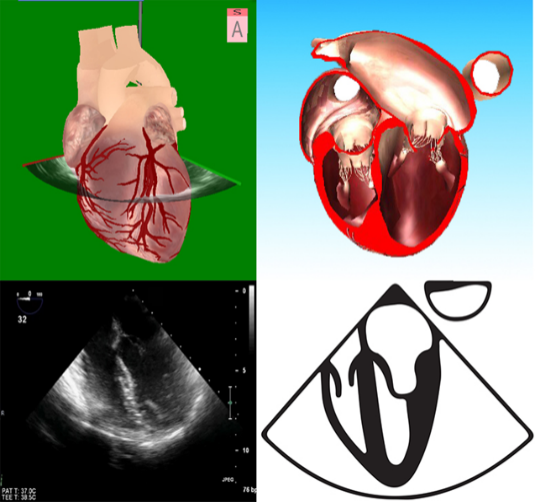

图2 2D和3D图像及成像原理 图3食管中段4腔心切面及模型图

2D或是3D图像(图2)都需要定义视角,采取面对心脏模型的视角,有2个理由:①面对心脏模型与系统解剖学方位一致,便于沟通;②面对心脏模型有利于实现从TEE到TTE的快速切换。以食管中段4腔心切面为例,描述探头与图像的位置关系理解图像和心脏模型的位置关系(图3),直观地显示了探头、切面与心脏模型的空间关系。